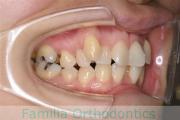

No.22V-269

- 過蓋咬合

- 上顎前突

- 20歳

- 女性

- 44

- 88

- FEA

- 90万円

左上の前歯の出っ歯が気になるということで来院されました。下あごの後退が非常に強く、外科矯正も選択肢の一つでしたが、矯正治療単独の治療をご希望になりました。上顎のみ左右小臼歯を抜歯して、マルチブラケット法を行いました。2年半、30回程度の通院が必要でした。

下あごの後退があるということは、上の前歯を大きく移動させないとかみ合わせが取れないということです。そのため、同部の歯根吸収のリスクが高いケースでした。